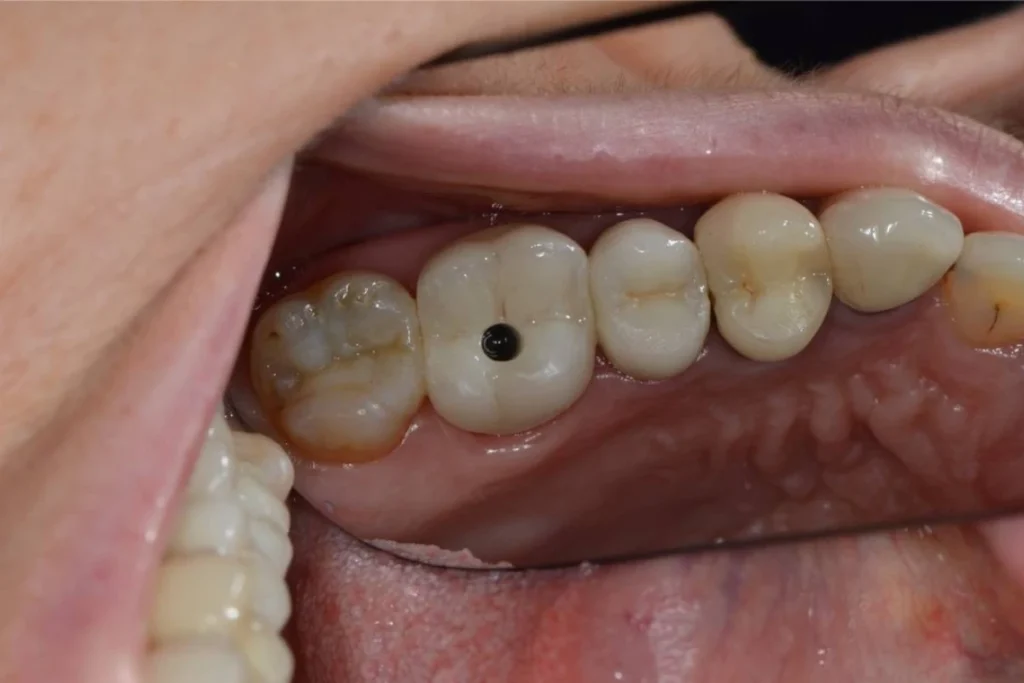

Cas clinique 2 – Remplacement d’une incisive latérale par un implant dentaire

Mr C. 40 ans vient nous consulter pour une visite de routine. L’examen clinique et met en évidence un infection sous une dent couronnée il y plusieurs années par un confrère. Le scanner réalisé au cabinet confirme la nécessité d’extraire cette dent et nous décidons de réaliser un protocole d’extraction implantation et mise en esthétique immédiate.

En clair, nous réalisons l’extraction de la dent, la mise en place de la racine artificielle ou implant et la fabrication d’une couronne provisoire en résine le tout lors de la même séance. Le patient repart du cabinet avec toutes ses dents!

Dans le cas présent, nous avons même pu répondre à la demande esthétique du patient en symétrisant son incisive latérale droite avec celle de gauche. L’intervention est réalisée sous anesthésie locale ce qui la rend parfaitement indolore.

Ce type de protocole est réalisé systématiquement au cabinet lorsque la situation nous le permet afin d’éviter à nos patients la galère d’un appareil provisoire amovible pour remplacer la dent absente. En contrepartie, le patient s’engage à respecter nos recommandations post opératoires pendant les semaines qui suivent l’intervention.